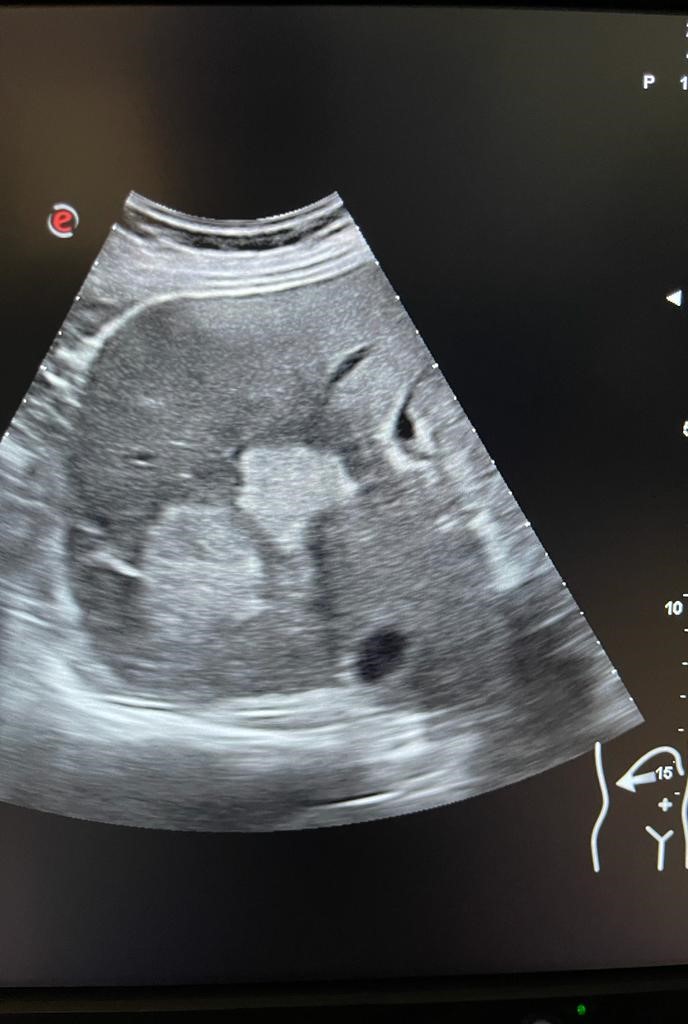

Se aprecia hígado heterogéneo con múltiples LOES hepáticas hiperecogénicas (una de ellas de unos 7x7 cm), sin captación de doppler. Al menos otras 2 LOES de menor tamaño presentan halo hipoecoico. Vesícula replecionada de contornos lisos y sin litiasis en su interior. Ambos riñones visualizados de tamaño normal y sin datos de hidronefrosis.